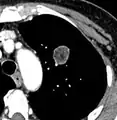

Lung nodule abutting a pulmonary cyst.[9]

• A lung nodule abutting a pulmonary cyst is a rare finding, yet indicating cancer.[9]